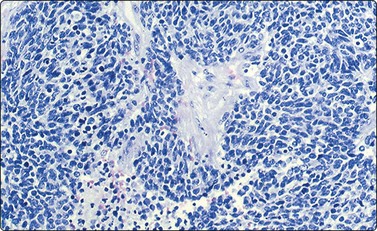

Neuroblastoma usually forms a well-defined solid tumor <10 cm in size with hemorrhage and extentive necrosis. The FNA usually yields hypercellular smears with predominant individually scattered small anaplastic cells, showing prominent nuclear molding.27,41,42 The prototypical neuroblastic cells have high nuclear to cytoplasmic ratios with single nuclei that are oval to slightly irregular in shape containing evenly dispersed granular chromatin (salt and pepper) and small to inconspicuous nucleoli (Fig. 17.1). Small round cells are arranged in moderately or well-formed Homer-Wright rosettes surrounding centrally located neuropil, which stains pink or blue–gray in Giemsa-stained smears. The presence of Homer-Wright rosettes is diagnostic but not present in all cases (Fig. 17.2). Neuropil, either associated with the rosettes or present in the smear background, is the most helpful cytologic feature for rendering a definitive cytologic diagnosis of neuroblastoma.34 Neuropil consists of a fibrillary tangle of neuritic processes with or without associated neuroblastic cells (Fig. 17.3). Mitotic–karyorrhectic cells and calcifications can occasionally be recognized in aspirate smears. Larger differentiating neuroblasts with moderate amounts of cytoplasm and binucleated to multinucleated ganglion cells can also be present in the smear. Some neuroblastomas may undergo different grades of maturation, forming ganglioneuroblastoma or ganglioneuroma. In ganglioneuroblastoma, the smear is pleomorphic with prominent anisonucleosis and abundant neuropil background but without ganglion cells, while ganglioneuroma demonstrates characteristic ganglion cells (Fig. 17.4).27,42

image

Fig. 17.1 Neuroblastoma

Hypercellular smears demonstrate numerous singly scattered cells with high nuclear to cytoplasmic ratios, round to oval irregular nuclei with fine granular chromatin and inconspicuous nucleoli (Diff-Quik, ×400).